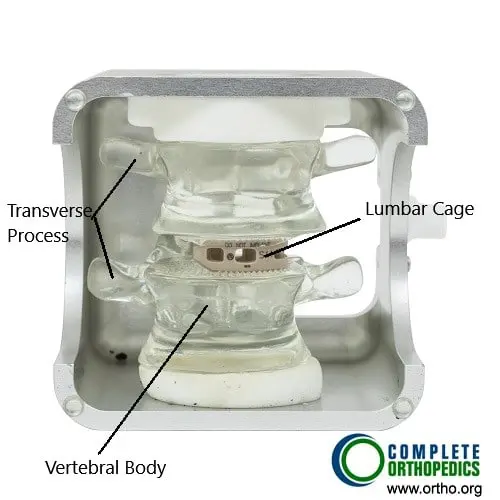

- Fusion surgery: Used when there is spinal instability, combining decompression with rods, screws, and bone grafts to stabilize the spine.

Transforaminal atraumatic lumbar interbody fusion cage

The image shows a lumbar fusion done with transforaminal technique. The fusion is aided by the bone cage which is filled with bone graft. The fusion of the segment results relief from symptoms of lumbar canal stenosis.